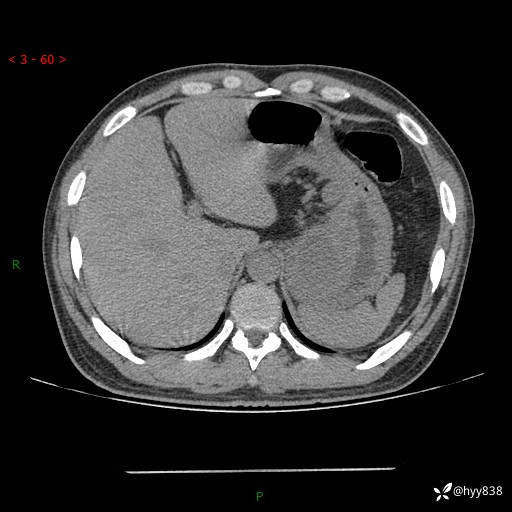

病例39岁/女,左侧腰痛入院。腹腔囊实性肿块,定位、定性---结果公布~

性别:男

年龄:39岁

简要病史:左侧腰痛待查,CT发现腹腔占位

腹部CT平扫+增强